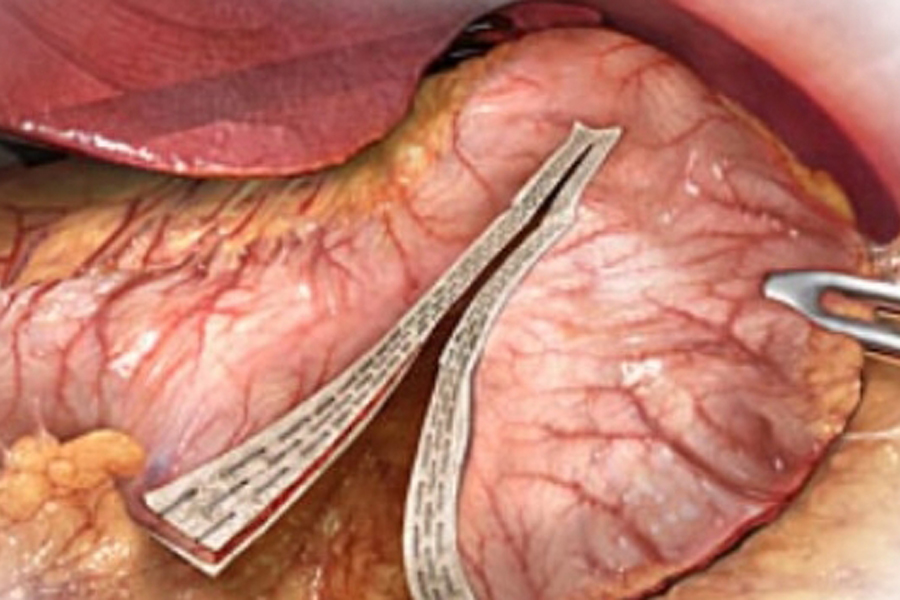

En la Gastrectomía Vertical Laparoscópica ha sido recomendado el refuerzo sero-seroso de la línea de sutura mecánica tras completar la gastrectomía con el objetivo de reducir el riesgo de hemorragia o la potencial fístula de la unión esófago-gástrica, sin embargo no se ha demostrado que disminuya claramente el riesgo de estas complicaciones.

En la actualidad existen múltiples procedimientos disponibles en cirugía de la obesidad. La banda gástrica ajustable laparoscópica (BGAL) ha sido una de las técnicas bariátricas más utilizadas. Ha demostrado ser un procedimiento seguro con una tasa de mortalidad muy baja y pocas complicaciones perioperatorias mayores.